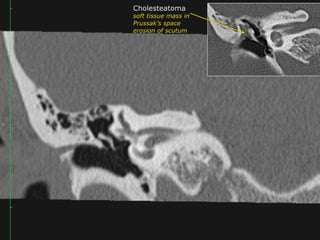

Acquired Cholesteatoma :

39 year old F with left conductive hearing loss.

Click to Return to Algorithm

A: CT Rt axial

B: CT Rt cor

C: CT Lft axial

D: CT Lft cor

Normal

Scutum

Soft tissue density within the

middle ear cavity. It

obliterates Prussak’s space

and erodes the scutum and

ossicles.

Clear

Middle

ear

cavity